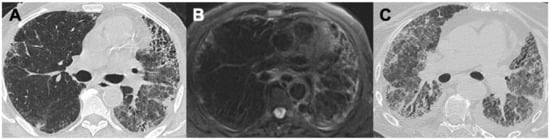

2.5. Eosinophilic Granulomatosis with Polyangiitis (EGPA)

| EGPA | Bronchial wall thickening; mucoid impaction, bronchiectasis | Tree-in-bud opacities; GGO; consolidations; diffuse alveolar hemorrhage (4%) | Pleural effusion | Dilatation of peripheral pulmonary arteries |